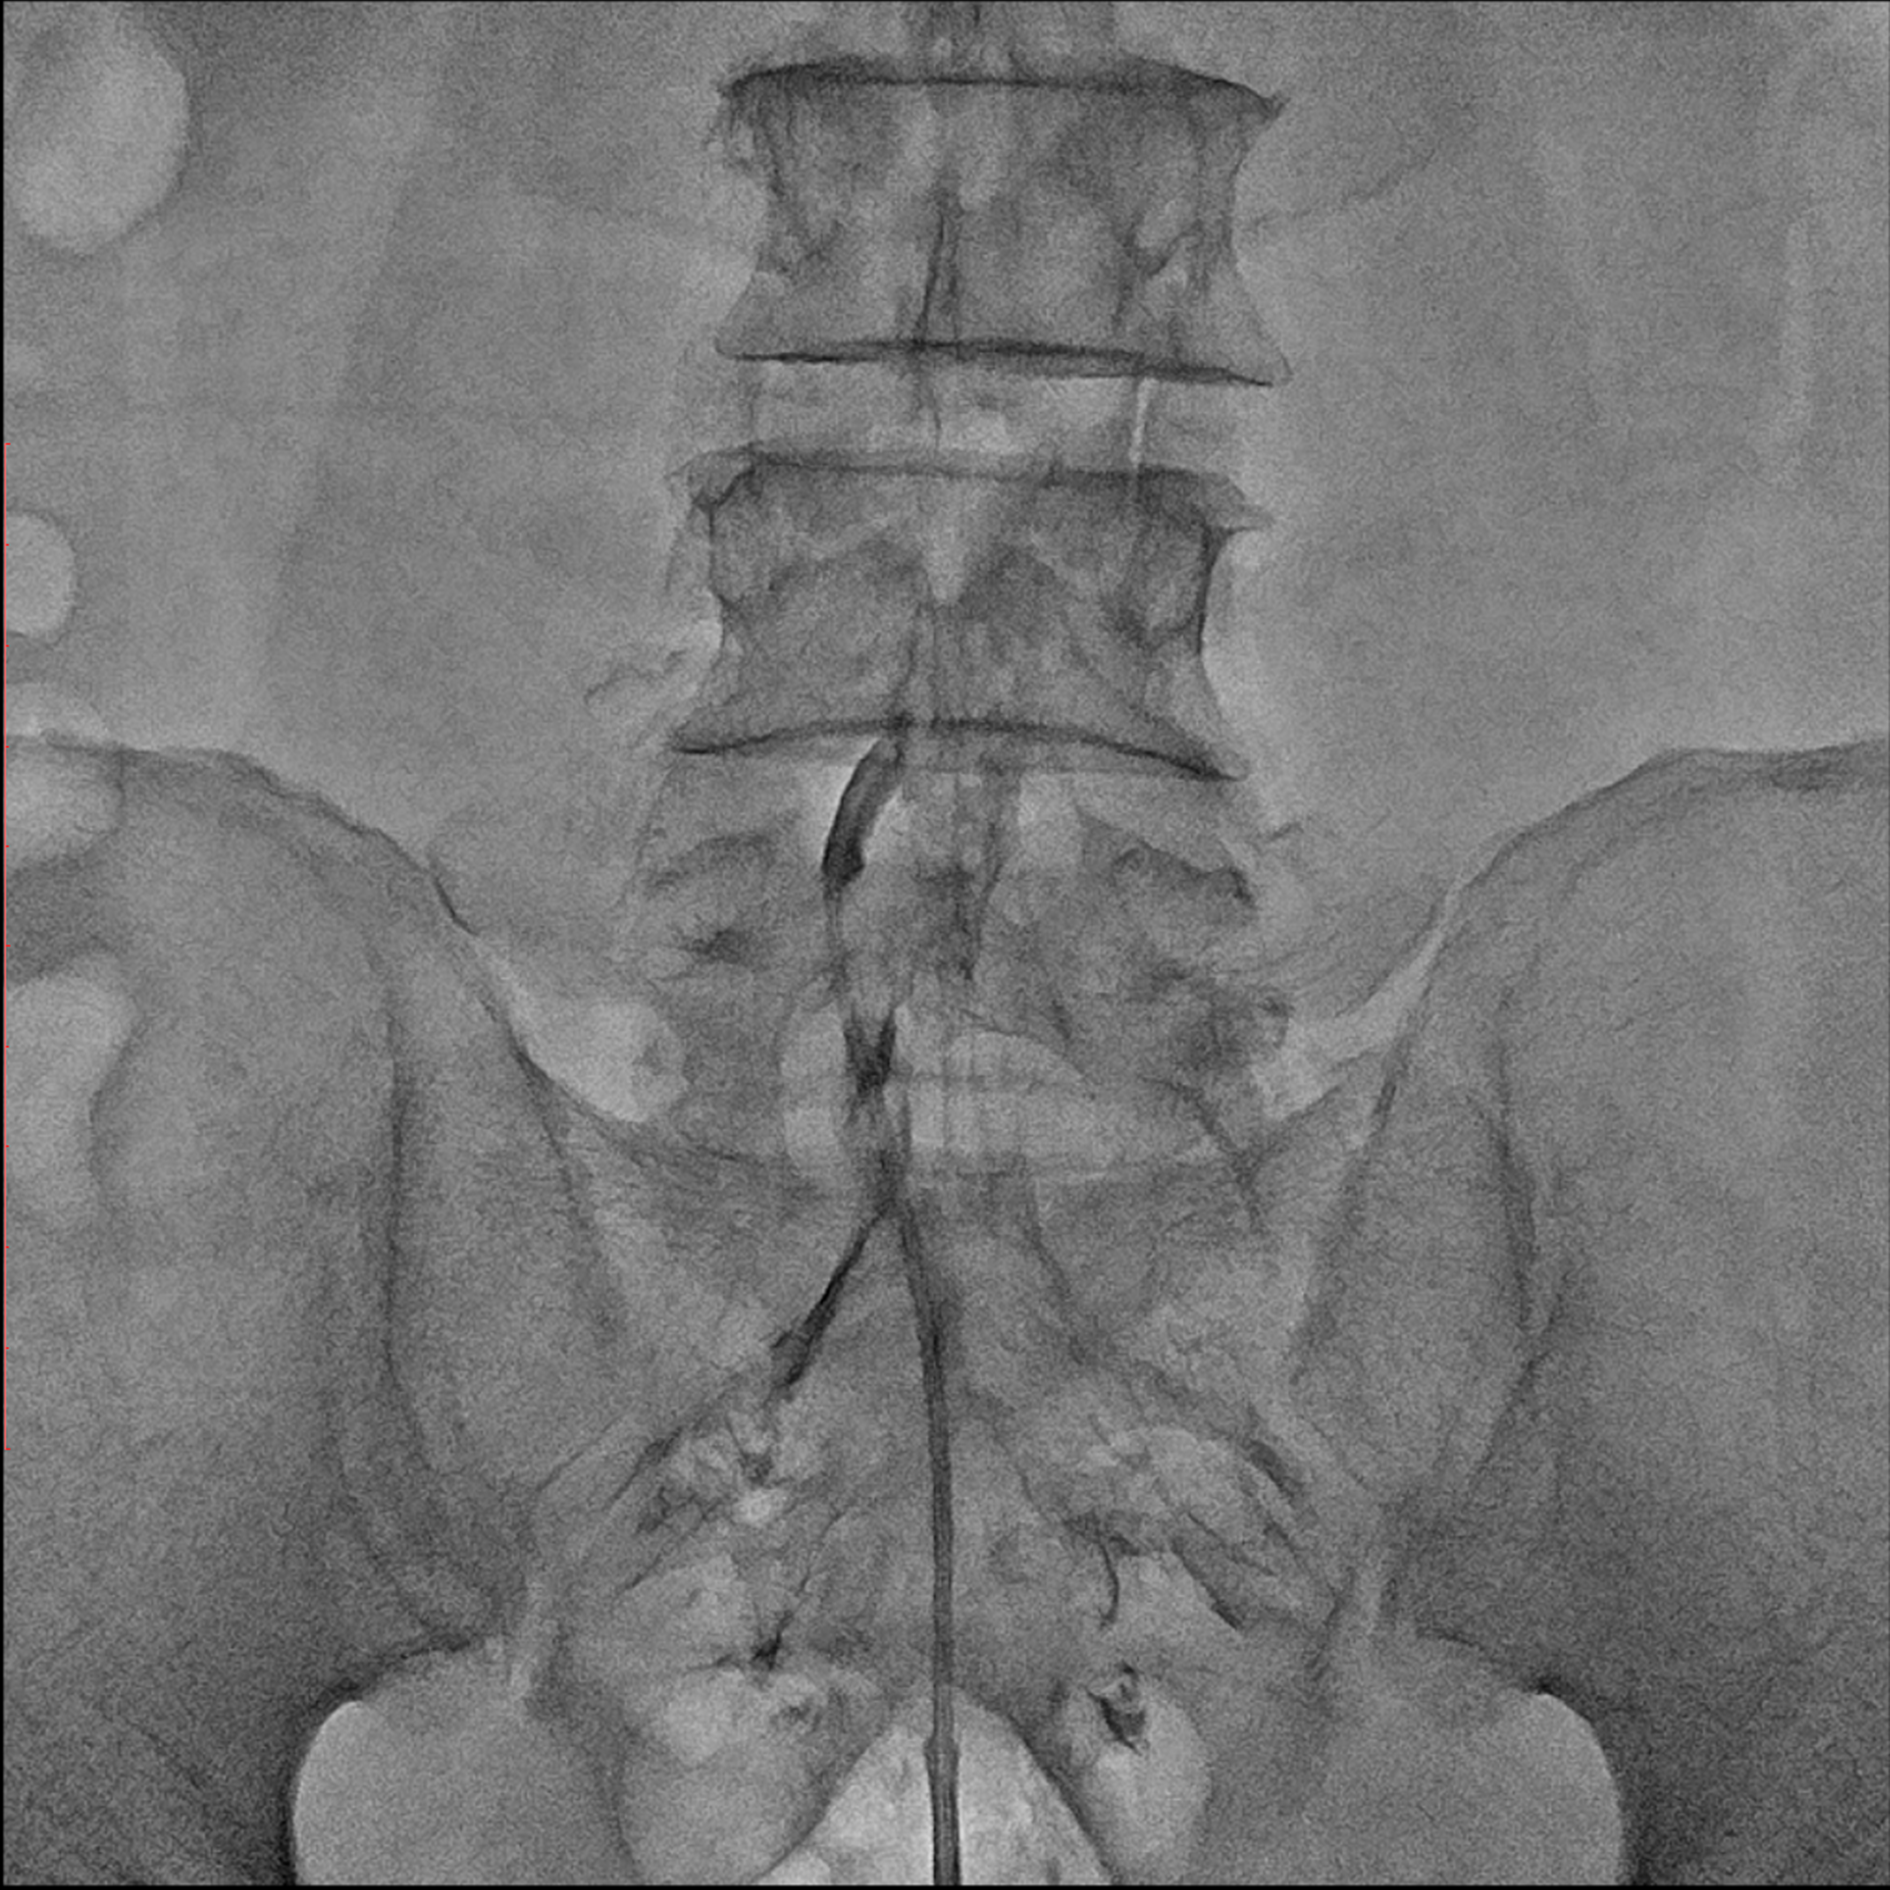

경막외 유착박리술, Epidural Neuroplasty